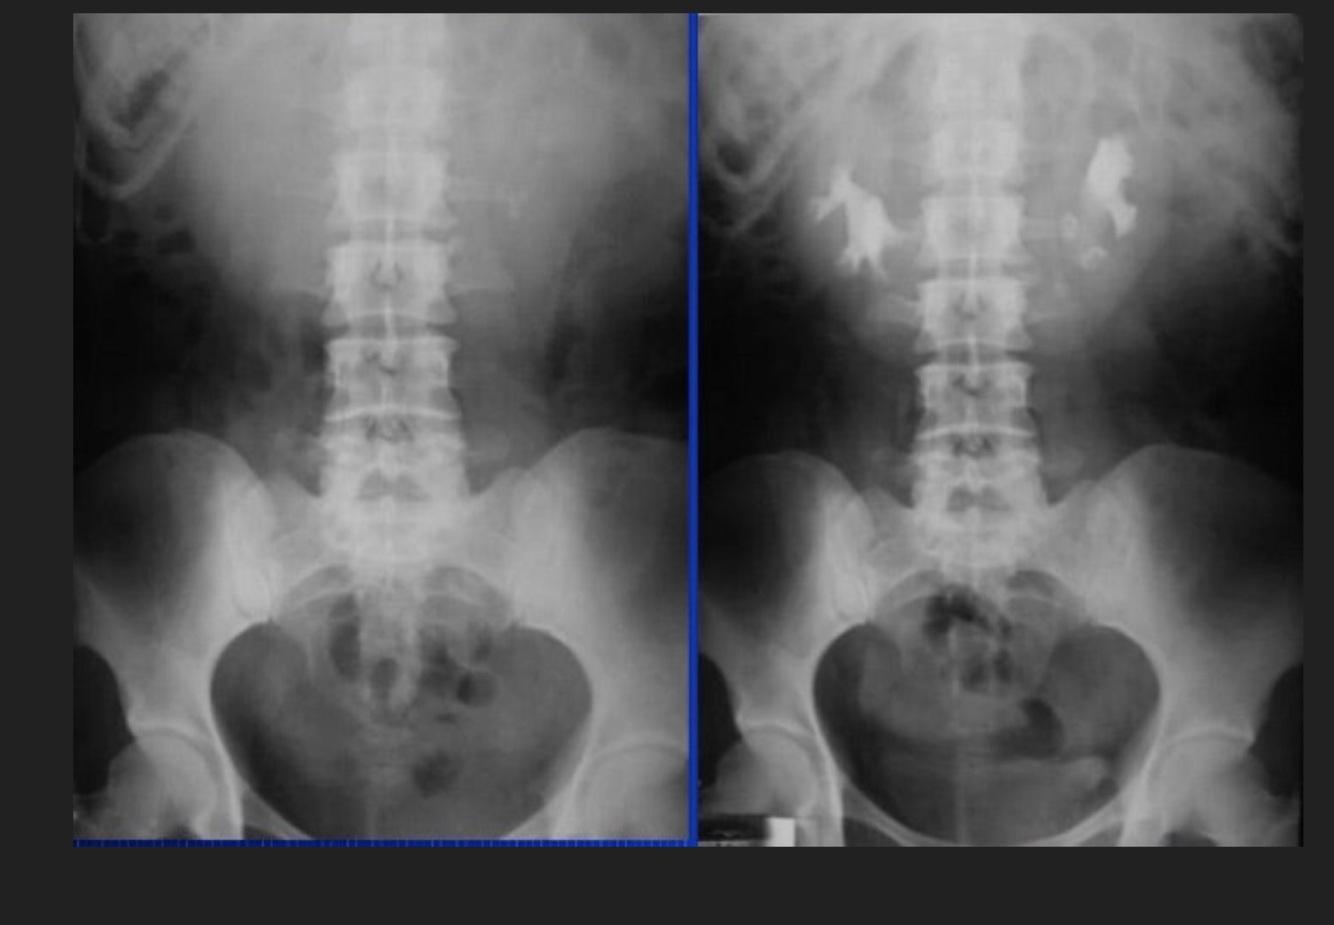

4

Q

UE Nefromegalia secundaria a:

A

Hidronefrosis

How well did you know this?